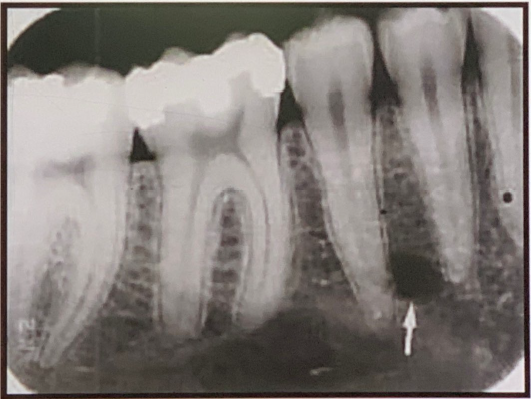

91. what does arrow show?

Mental Foramen the anterior limit of the inferior dental canal that is apparent on periapical radiographs. seen about halfway between the lower border of the mandible and the crest of the alveolar process, usually in the region of the apex of the second premolar. (may be projected anywhere from just mesial of the permanent first molar roots to as far anterior as mesial of the first premolar root) When the mental foramen is projected over one of the premolar apices, it may mimic periapical disease .